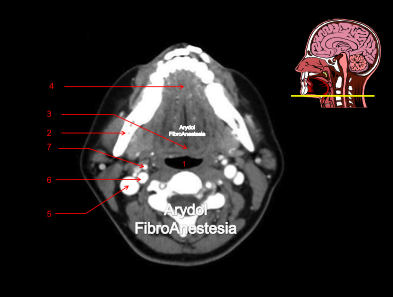

CORTE A NIVEL DEL SUELO DE LA BOCA

1.orofaringe; 2.mandíbula; 3.base de la lengua; 4.suelo de la boca; 5.vena yugular interna; 6.arteria carótida interna; 7.arteria carótida externa